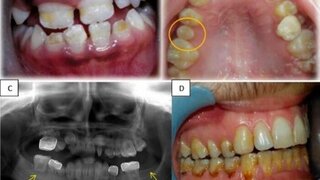

Studie aus IsraelZahnentwicklungsanomalien nach Krebserkrankungen im Kindesalter Die kombinierte Chemo- und Strahlentherapie – insbesondere bei einer Bestrahlung im Kopf-Hals-Bereich – birgt ein hohes Risiko für das spätere Auftreten von Zahnentwicklungsanomalien, so eine Studie aus Israel. Ausgabe 10/2022ZahnmedizinKinderzahnheilkunde

Studie aus IsraelZahnentwicklungsanomalien nach Krebserkrankungen im Kindesalter Bei rund der Hälfte der Überlebenden von Krebserkrankungen im Kindesalter treten später Zahnentwicklungsanomalien (DDA) auf. Dabei beeinflusst die Art der Therapie das Auftreten einer DDA maßgeblich. 26.04.2022 ZahnmedizinKinderzahnheilkunde